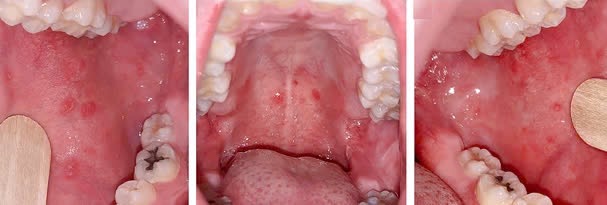

- Giai đoạn khởi phát (giai đoạn viêm long): trong 2 - 4 ngày. Trong giai đoạn này người bệnh sốt cao (trên 390C), có thể có biểu hiện triệu chứng ho, sổ mũi (viêm long đường hô hấp trên) hoặc viêm kết mạc mắt hoặc có tiêu chảy Ở giai đoạn này có thể thấy hạt Koplik là các hạt nhỏ có kích thước 0,5 - 1 mm màu trắng/xám có quầng ban đỏ nổi gồ lên trên bề mặt niêm mạc má (phía trong miệng, ngang răng hàm trên). Hạt Koplik thường xuất hiện một ngày trước phát ban và tồn tại 2 - 3 ngày sau khi ban xuất hiện.

Hạt koplik (Nguồn: Internet)